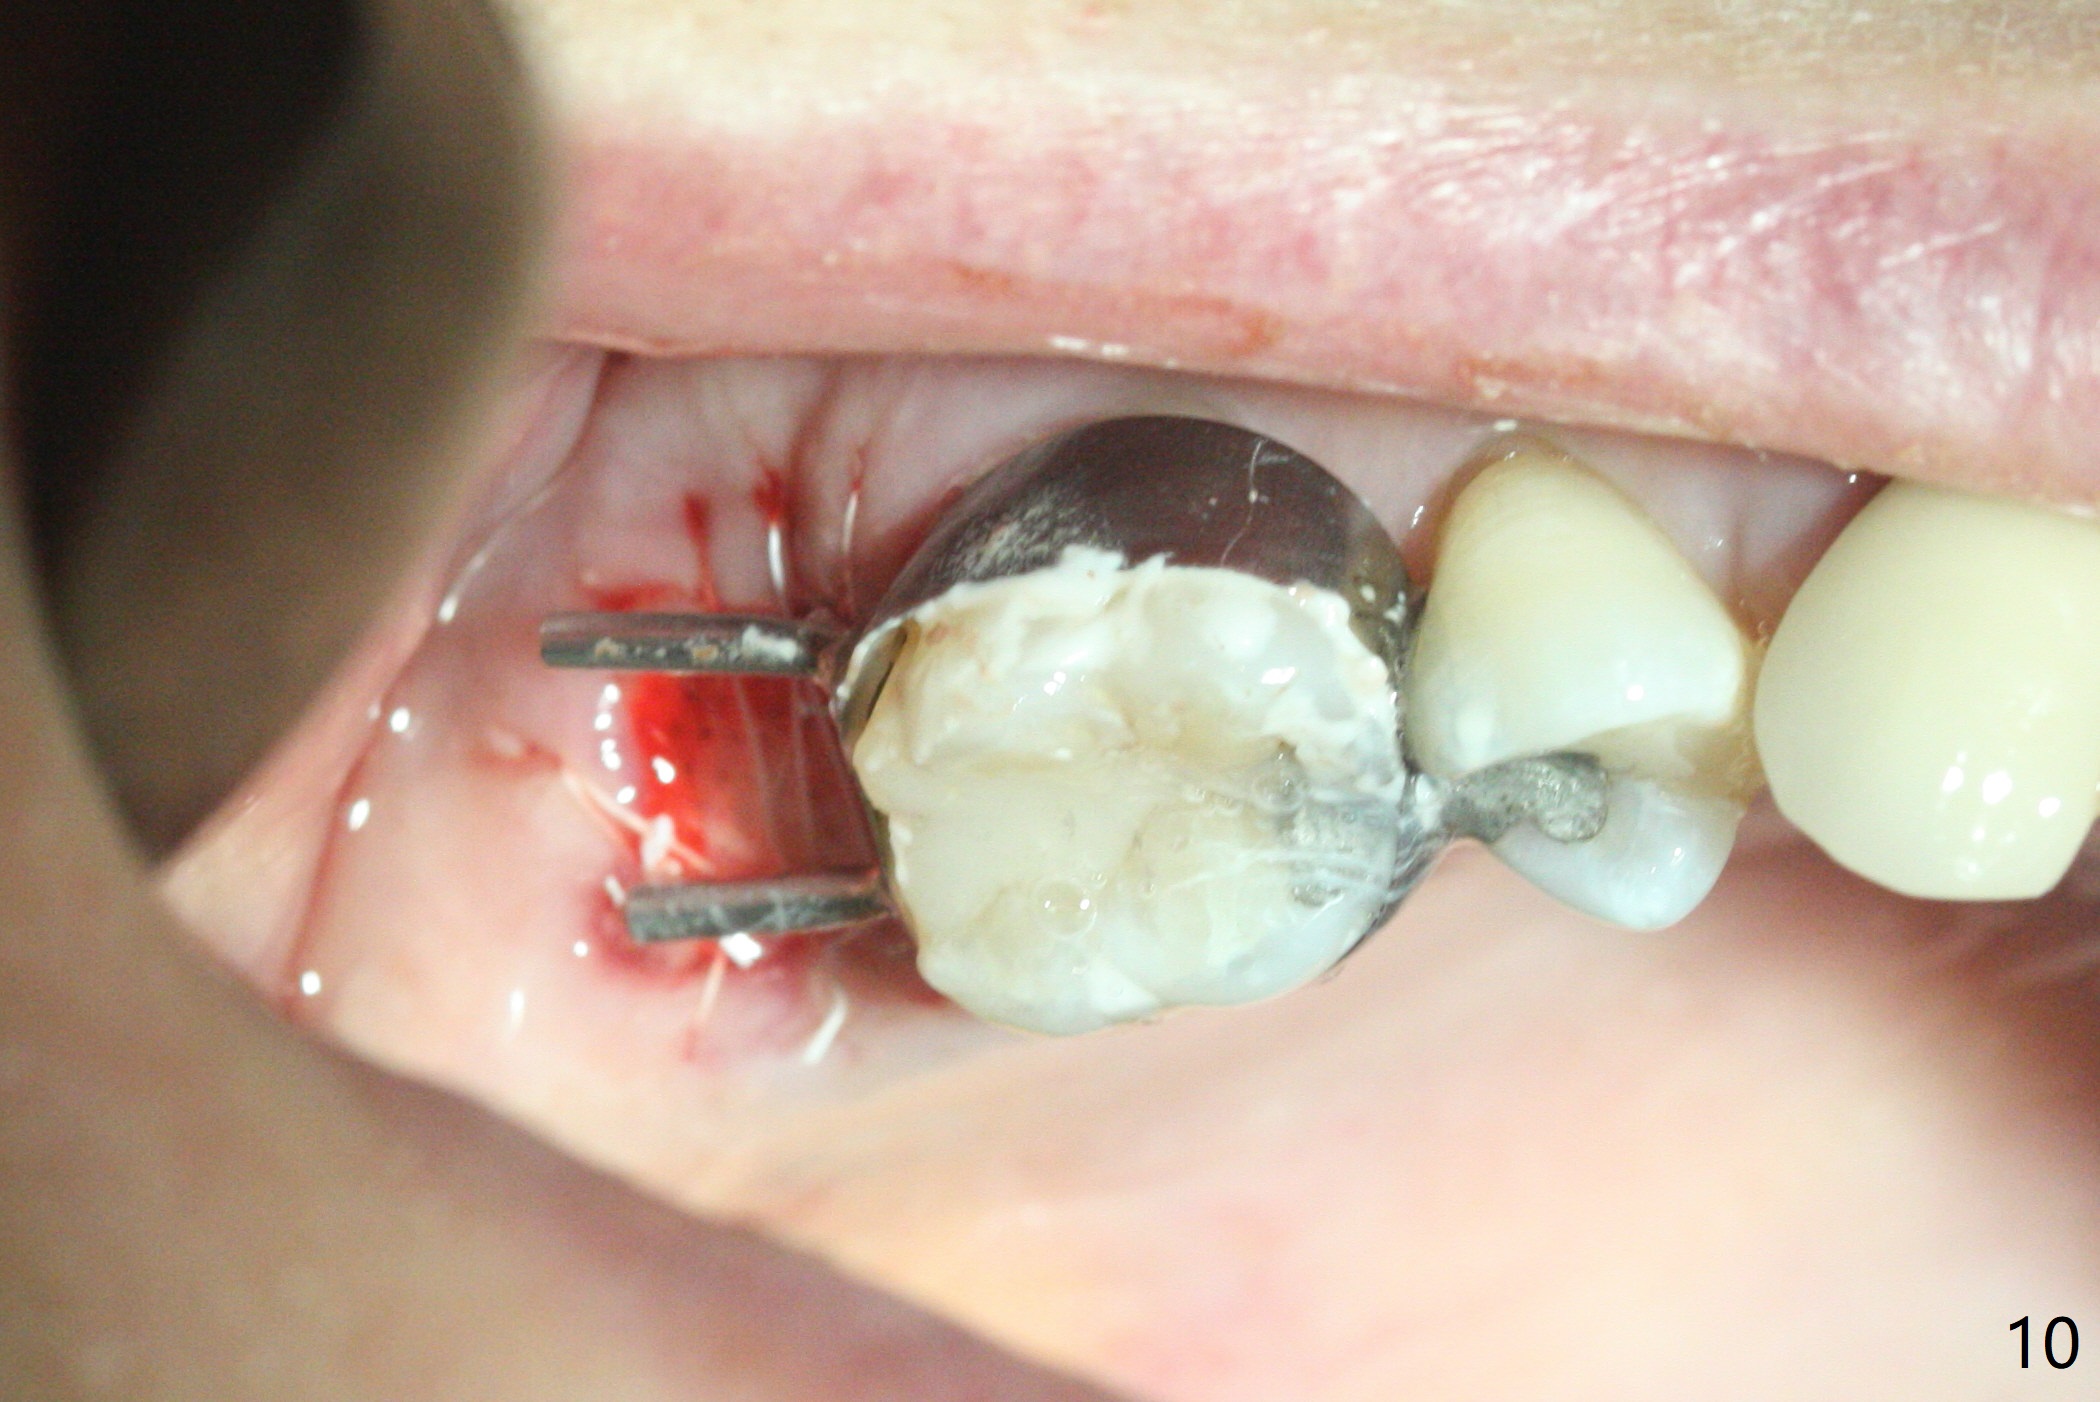

第二磨牙位点保留后,牙周敷料容易脱落,尤其上颌,本文介绍一种方法增加固位。右上七严重牙髓牙周综合征,拔出后使用刮匙除去骨面肉芽组织,颊侧骨板缺失,附着在颊侧粘骨膜上的肉芽组织使用一种叫Stieglitz angled, diamond splinter forceps (德国产,图一,二)撕下来。彻底清除炎性组织必须多次刮治,之间塞入带有灭滴灵(图三:粉剂)和1比50,000肾上腺素局麻药纱布(图四)止血,取出纱布,牙槽窝视野好,继续去除残余的肉芽组织。牙槽窝底部穿孔,用无齿刮匙稍微扩大穿孔后,使用图五下面小的骨粉输送器,将少量骨粉(粘性)送到穿孔处,推入上颌窦(图七:S),之后使用大的骨粉输送器(图五上面),把大量骨粉送到牙槽窝,使用图六上面大的,长的充填器,压实骨粉(图七),骨粉表面放置PRF膜和不可吸收膜(图八),在第一磨牙时安置粘固一个间隙维持器(图九,十),最后铺上牙周敷料(图十一),检查咬合空间,没有干扰。There are sign and symptom of sinusitis 1 week postop; large amount of bone graft retains in the socket by the periodontal dressing and spacer (Fig.12). The sinus membrane (Fig.7 immediate postop) thickens 1 week postop (Fig.13). Augmentin and Medrol Dose Pak are prescribed. 上颌窦炎一周后消失,腭侧牙周敷料丢失,伤口好像正常愈合(图十四)。术后三周牙周敷料由于大量水枪冲洗脱落(图十五)。因为病人需要离城两个月,间隙保持器撤除(图十六),不可吸收膜腭侧稍微外翻 (<),可能有利于术后五周自行脱落。No Deviation SP 下一个病例 位点保留后Xin 导板与张口度 第一磨牙即种 Wei, DDS, PhD, MS 1st edition 09/17/2020, last revision 04/30/2021